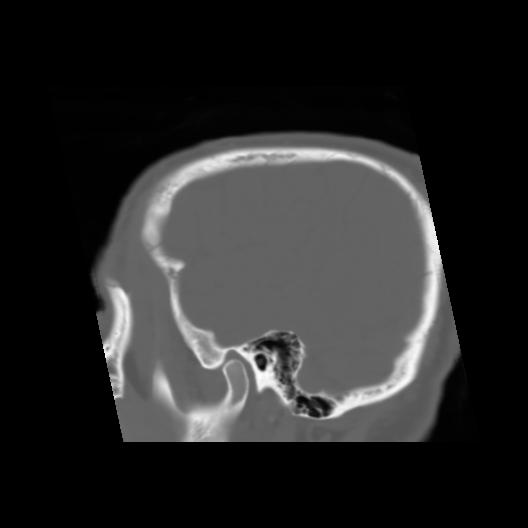

6 CEREBRO,,Sagittal,3.000,CEREBRO,Sagittal,